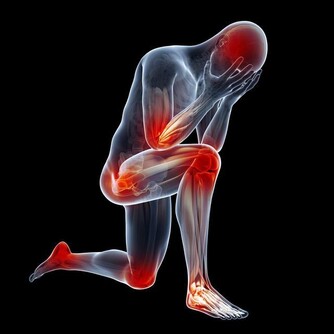

針對上樓疼、下樓疼、下蹲困難,等各種膝關節疼痛等都有效!

髕骨軟骨軟化的症狀

疼:上下樓會痛,膝關節突然打軟無力。有時候是半蹲發力時疼,尤其是搬重物的時候。嚴重的日常生活的活動中就會疼,走路的時候都有膝關節打軟腿的現象。另外,如果用手按摩髕骨的邊緣,常常有明顯壓痛。

響:膝關節屈、伸活動時,髕骨下面常常會出現響聲,嚴重的患者,自己坐著伸直腿,把手放在髕骨上,壓著髕骨摩擦一下,就能聽到“沙沙”的響聲,像關節裡面有沙子一樣。

腫:因為關節內部的炎症,導致關節滑膜分泌出很多液體,所以表現出膝關節腫脹。

細:髕骨軟化,會導致股四頭肌肌肉萎縮,疲軟、所以大腿外觀會變細。